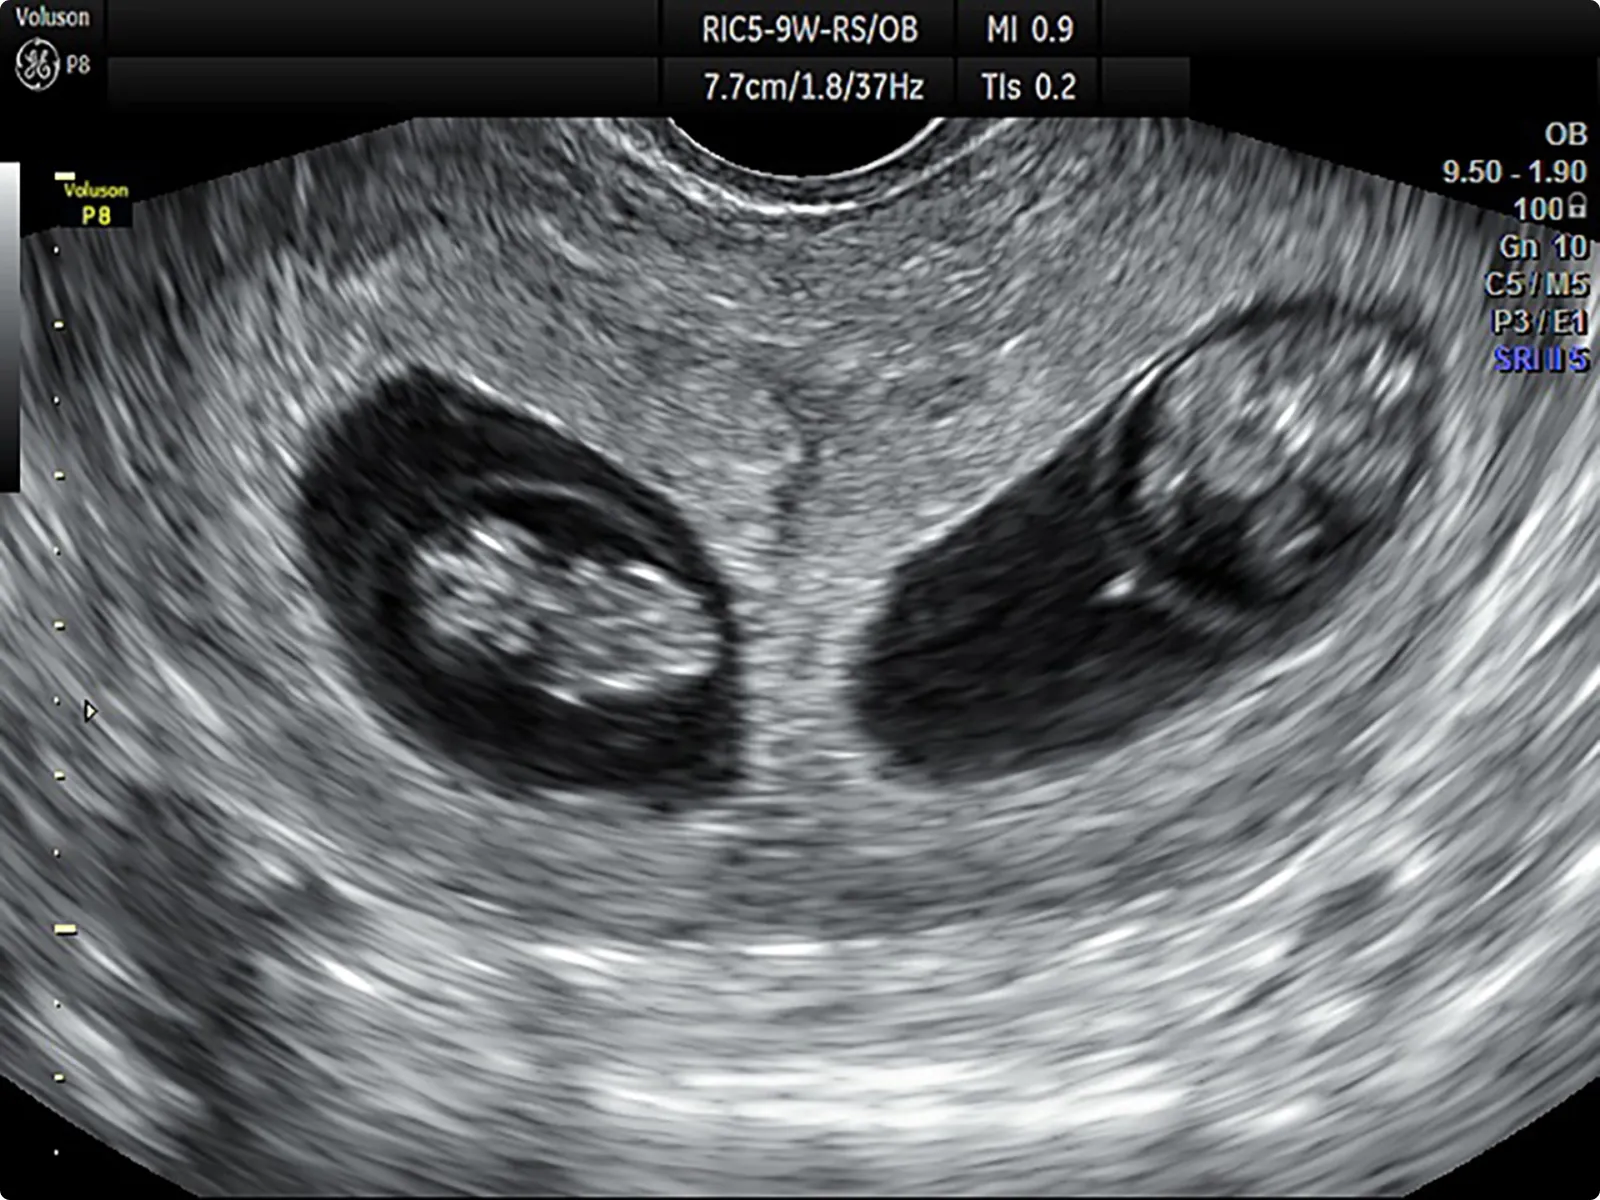

① 二絨毛膜二羊膜双胎(DD双胎)

胎児の部屋、胎盤がそれぞれに分かれています。1卵性でも起こりますが、2卵性の場合は通常このタイプなので、複数卵胞発育や複数胚移植をした場合に起こりやすいと考えられます。

特にARTによるDD双胎では自然妊娠のDD双胎よりも前置胎盤、早産、低出生体重児、先天異常のリスクが高いという報告もあります。

DD双胎